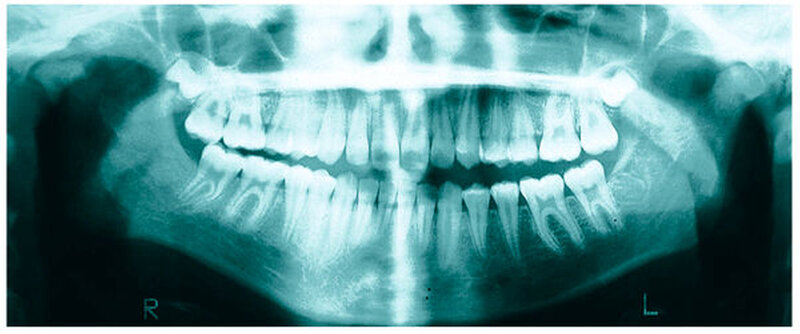

Bereits 2004 wies Carla Evans [Evans, 2005] auf das Risikomanagement bei Allgemeinerkrankungen hin und stellte am Beispiel der JIA dar, dass Unterkieferrücklagen und frontal offene Bisse aus der Kiefergelenkzerstörung entstehen können. Die Röntgenaufnahmen einer JIA-Patientin mit oligoartikulärer Form und Beteiligung des rechten Kiefergelenkes zeigen den typischen Verlauf sehr gut. Bei ursprünglich sehr dezenten Befunden, wie einer s-förmigen Mundöffnung von 44 mm, einer geringen Mittenabweichung um 2 mm nach rechts und einem frontal offenem Biss klagte sie über Schmerzen beim Essen, was den Anlass zur weiteren Diagnostik bot. Die erste Panoramaröntgenschichtaufnahme (Abbildung 1a-c) zeigt auf der rechten Seite einen abgeflachten Kondylus und eine bereits verstrichene Fossa condylaris. Ein Jahr später vermittelt das Fernröntgenseitenbild (Abbildung 1d) trotz fortschreitender kondylärer Resorption ein harmonisches Bild, während nach drei Jahren bei voranschreitendem Abbau des rechten Kondylus (Abbildung 1e) eine Rücklage der Mandibula und eine Bissöffnung manifest sind (Abbildung 1f).

Mithilfe der Panoramaröntgenschichtaufnahme lässt sich in bis zu 67 Prozent der Fälle bereits eine Kiefergelenkdestruktion bei Kindern mit JIA feststellen [Küseler et al., 1998; Twilt et al., 2004; Abramowicz et al., 2014]. Eigene Untersuchungen bestätigten die Eignung als Screening-Verfahren [Mäckelmann, 2008].

Bei 152 durchschnittlich 12-jährigen Rheumapatienten wurden die kondyläre Morphologie und Symmetrie beziehungsweise Asymmetrie im Vergleich zu einer Kontrollgruppe anhand der OPG analysiert. Zur Analyse erfolgte die Zuordnung zu vier morphologischen Graden je Kondylus (Abbildung 3a-d). Bei 45 Prozent der Rheumapatienten waren morphologische Veränderungen im Rahmen kondylärer Resorption unterschiedlicher Ausprägung zu finden. Die „Kontrollpatienten“ ohne JIA zeigten nur zu 14 Prozent formatypische Kondylen. Der Unterschied zwischen den beiden Gruppen war signifikant. Daher sollte bei der Routineauswertung von Panoramaröntgenschichtaufnahmen auf diese Anzeichen geachtet werden, insbesondere auch unter dem Aspekt, dass laut Assaf [2011] durchschnittlich 4,3 Jahre zwischen Erstmanifestation der JIA und Erstvorstellung in der Rheumasprechstunde des UKE liegen.